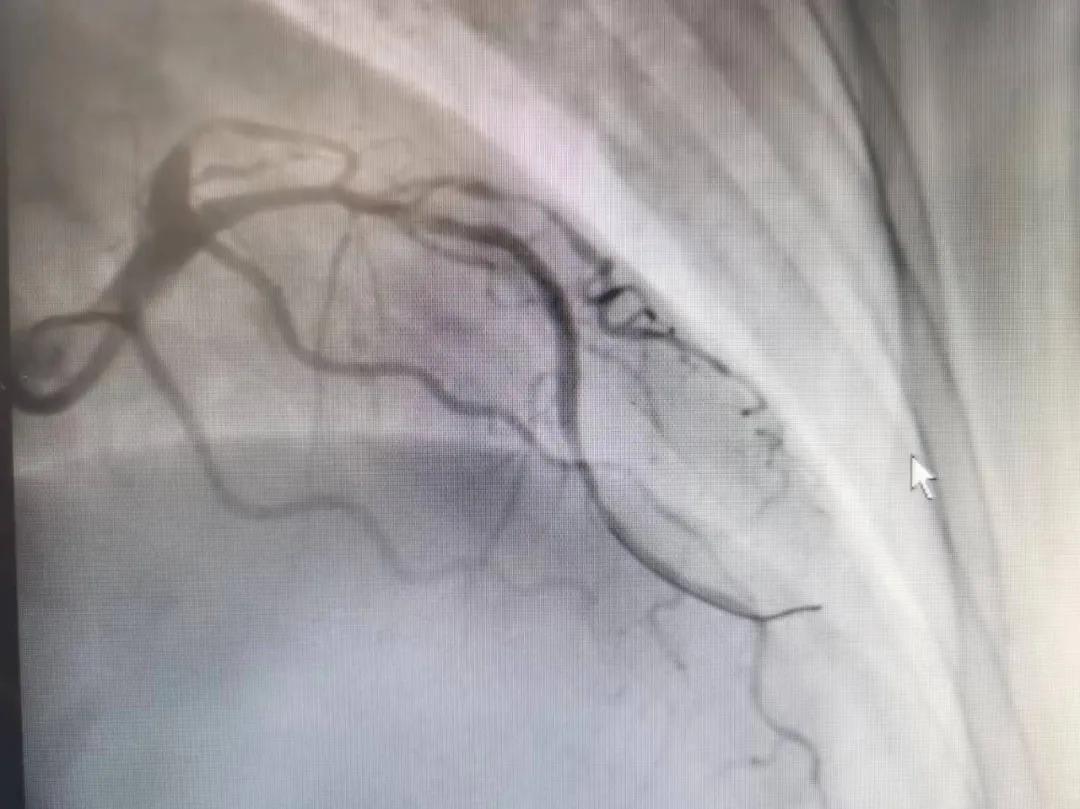

病人是位六十多歲的女性患者,有長期高血壓病史,1個月前開始出現(xiàn)胸悶胸痛,口服藥物治療效果不佳,經(jīng)朋友介紹,來到市二院心血管內(nèi)科。入院后完善冠狀動脈造影提示:前降支全程彌漫性狹窄伴鈣化,最重95%,回旋支狹窄約85%,右冠脈全程狹窄伴鈣化,最重60%。血管內(nèi)超聲顯示右冠脈開口面積3.36mm²,可見環(huán)形鈣化,考慮患者病變程度重、鈣化明顯,常規(guī)器械無法實現(xiàn)病變的良好預(yù)處理,且有很高的冠脈穿孔、血管夾層的風(fēng)險。

術(shù)前

王瑾院長和李慧新主任帶領(lǐng)介入團隊充分評估,決定行前降支冠狀動脈鈣化病變旋磨術(shù),術(shù)中應(yīng)用1.5mm旋磨頭,以15萬-17萬轉(zhuǎn)/分速度共對病變旋磨3次,累計旋磨時間60秒,后復(fù)查造影示鈣化明顯減輕,為后續(xù)操作創(chuàng)造了良好條件,隨后應(yīng)用預(yù)擴張球囊、切割球囊再次處理病變,并順利植入支架1枚,復(fù)查造影顯示支架膨脹及貼壁良好,無夾層、血腫、慢血流等情況,手術(shù)順利完成?;颊咝g(shù)后無不適,胸悶、胸痛癥狀明顯緩解,順利出院。